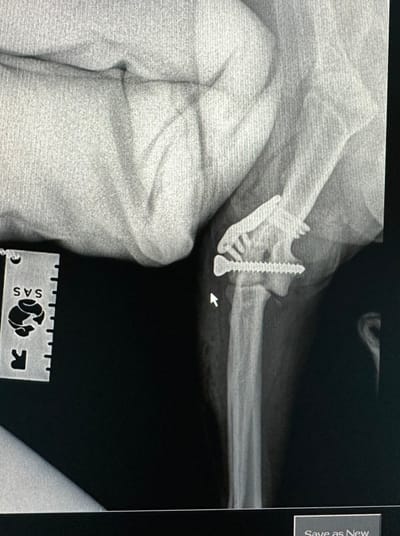

Lateral Condylar Fracture on a Spaniel

Repaired with intercondylar screw and LEAP ( Lateral Epicondylar Anatomical Plate ) - Surgeon Andre Pereira